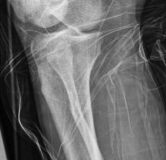

Tibial shaft fractures extending into the distal metaphysis and the tibial plafond represent a formidable challenge in orthopedic trauma. Historically, these complex injury patterns—often classified as AO/OTA 43-B or C, or 42 with distal extension—were managed primarily with plate osteosynthesis due to concerns regarding articular congruity and the inability of early generation intramedullary nails to secure short distal segments. However, the evolution of intramedullary nailing systems, featuring multi-planar distal locking options and advanced insertion trajectories, has revolutionized the management of these fractures.

The epidemiology of these injuries demonstrates a bimodal distribution. High-energy trauma, such as motor vehicle collisions and falls from height, typically afflicts younger patients and presents with significant soft tissue compromise, comminution, and complex articular involvement. Conversely, low-energy torsional mechanisms are more frequently observed in the elderly population, often resulting in spiral fracture patterns that propagate into the joint.